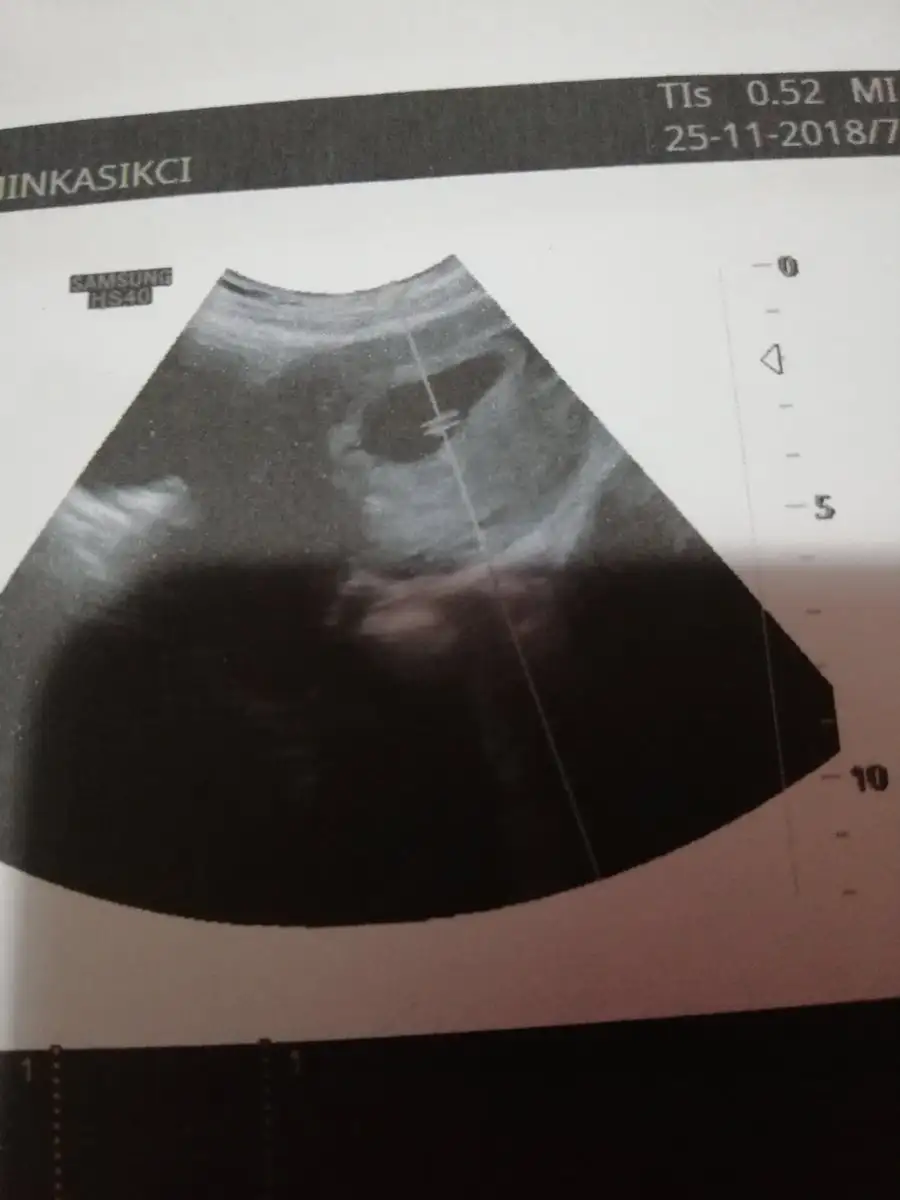

Çok teşekkür ederim Rabbim gonlunuzden geçeni kabul etsin USG görüntümüz karındanGözün aydın :) kese konumuna göre sağ da mıydı solda mı ? Benim kızım sağdaydı. Bu gebelikte solda. Kızlar Buda kız dedi ama ben erkek hissediyorum![]()

Çok teşekkür ederim Rabbim gonlunuzden geçeni kabul etsin USG görüntümüz karından

Ortada gibi burda :) amin sağol canım hepimizin inşallahÇok teşekkür ederim Rabbim gonlunuzden geçeni kabul etsin USG görüntümüz karından